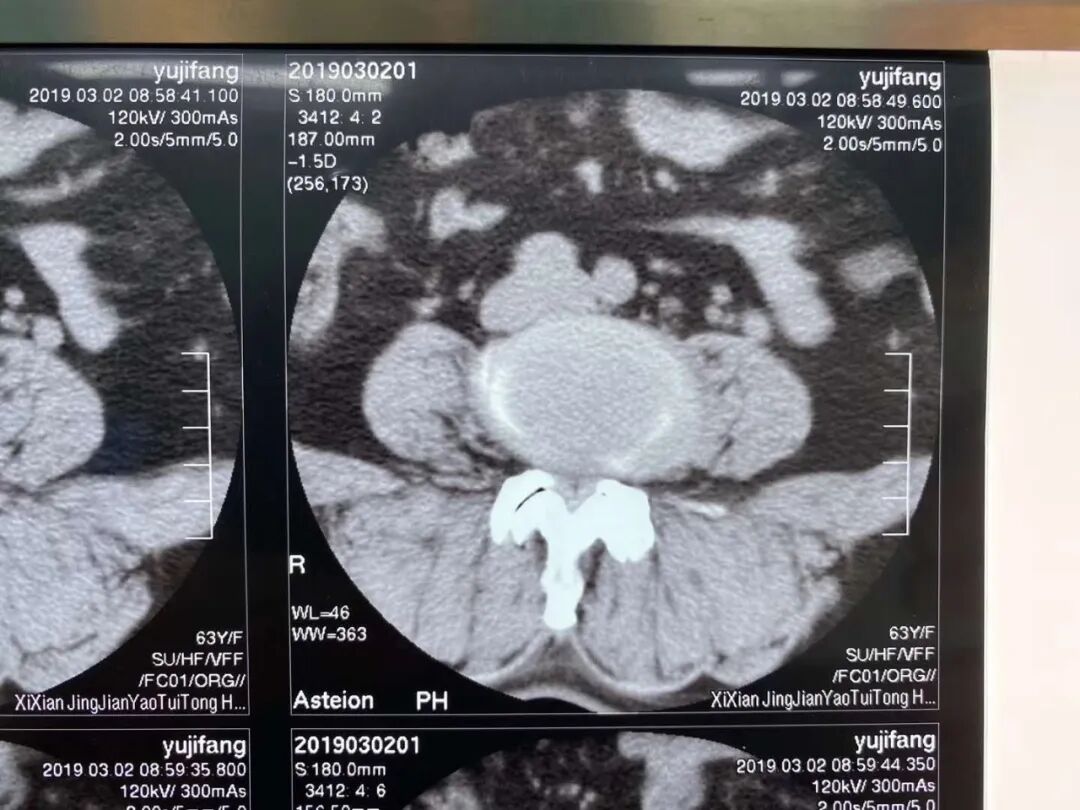

▲2020年5月9日,一例腰3/4严重椎管狭窄病例,采用单边双通道UBE技术来完成椎间盘减压。

▲患者病情影像